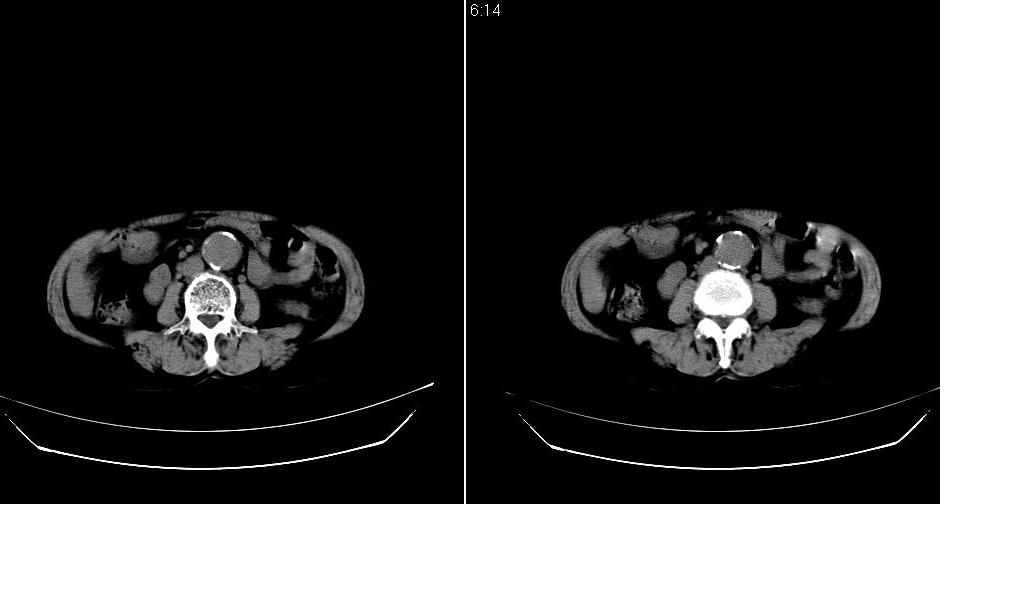

标题: CT12001:上腹部CT平扫

女73岁,病史不详,腹主动脉增宽.

考虑:腹主动脉瘤。建议增强。

考虑:腹主动脉瘤。建议增强排除夹层的可能。

考虑主动脉夹层,可惜没有增强,标识